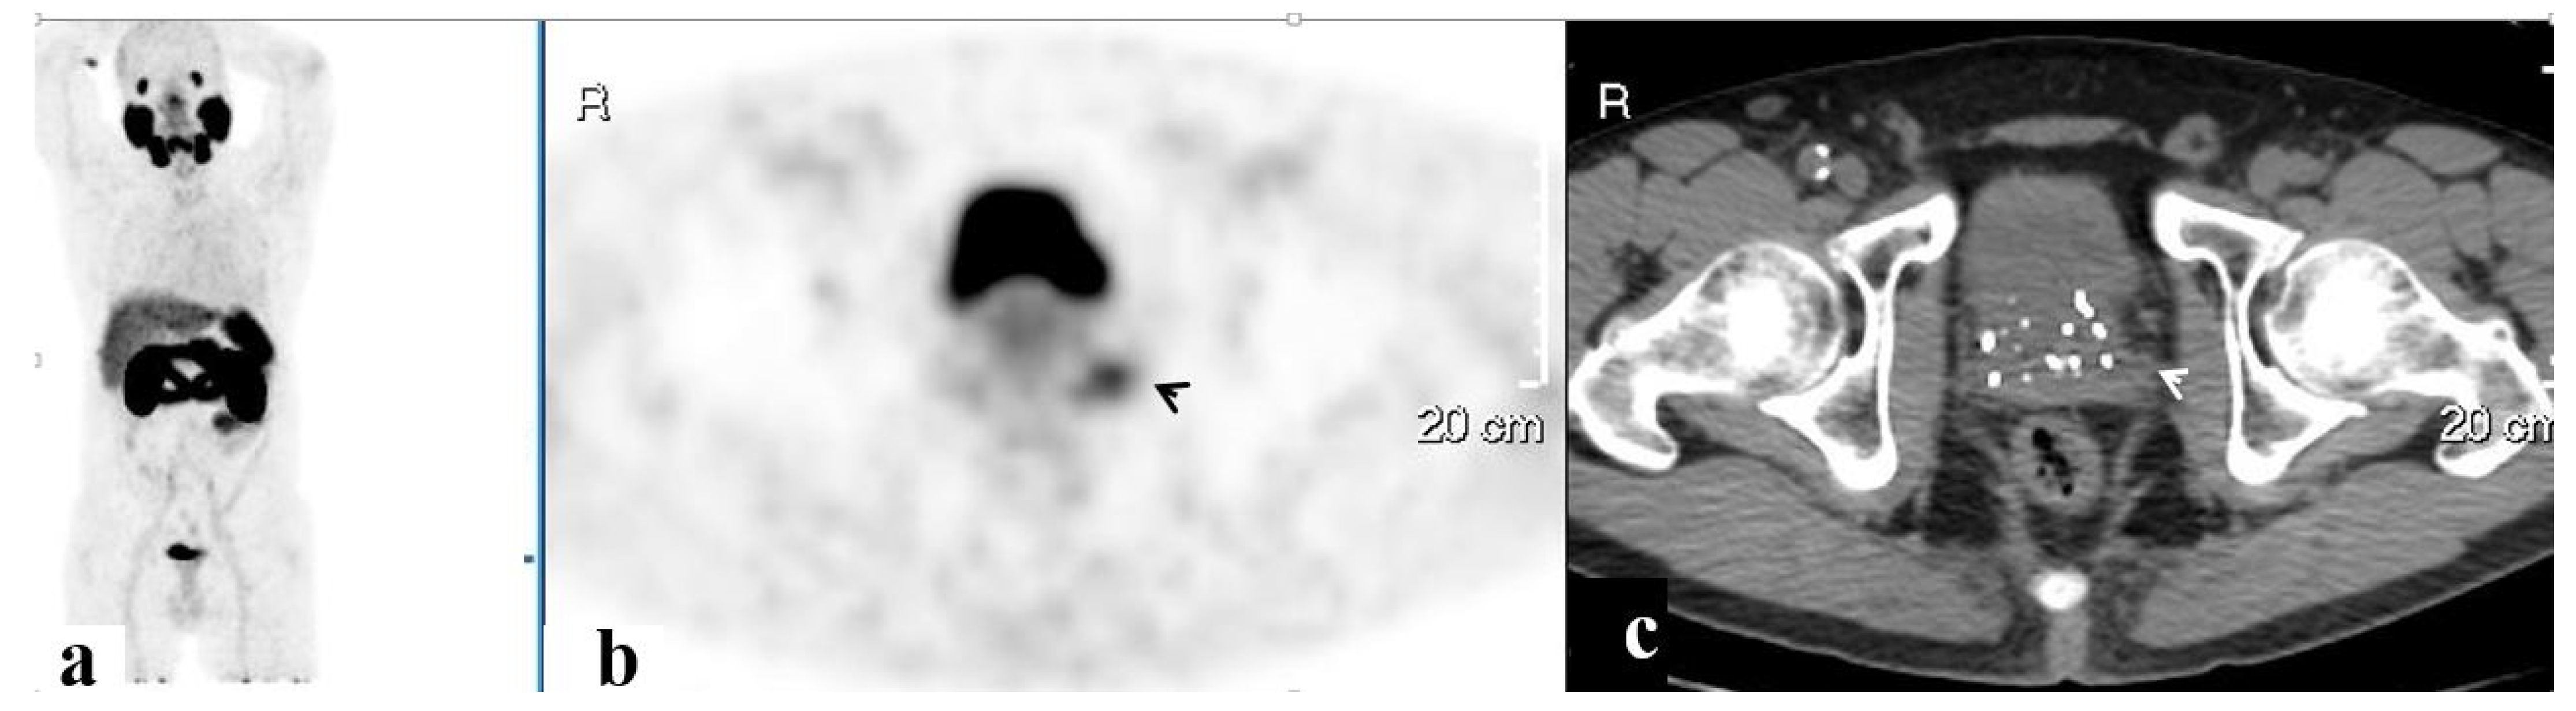

| Site | No. of Men | Mean SUVmax 1 | Mean Lesion Size (mm) 1 | No. Accompanied by LN |

|---|---|---|---|---|

| Isolated pelvic LAD | 43 | 11.0 ± 11.5 | 1.0 ± 0.3 | n/a |

| Prostate | 37 | 10.0 ± 6.4 | 2.1 ± 1.1 | 11 |

| SV | 23 | 8.6 ± 5.9 | 0.5 ± 0.5 | 7 |

| Pelvic bones | 16 | 14.2 ± 18.2 | 2.0 ± 1.0 | 2 |

| PF | 7 | 5.8 ± 5.6 | 1.4 ± 0.4 | 2 |

| SVF | 3 | 6.0 ± 1.6 | 1.3 ± 0.4 | 1 |

| Other 2 | 6 | 8.0 ± 3.2 | 1.3 ± 0.4 | 2 |